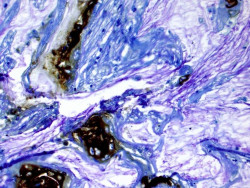

Una variedad diversa de bacterias viven en la boca humana como parte de un ecosistema vital conocido como el microbioma oral. Los investigadores del Instituto Politécnico y Universidad Estatal de Virginia (Virginia Tech) han descubierto que una de estas bacterias comunes del microbioma oral puede salir de la boca y potencialmente causar la propagación de las células cancerosas existentes en otras partes del cuerpo.